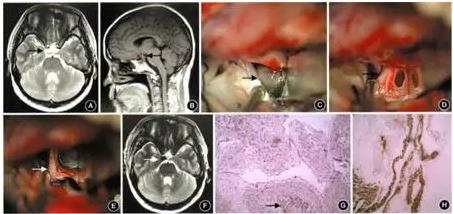

患者女,41岁。因“无明显诱因右侧眼睑下垂1周”于2015年8月5日入院。体检:意识清醒,言语正常,视力正常,双侧瞳孔不等大,右侧5 mm,左侧3 mm;左侧对光反射灵敏,右侧对光反射消失;右侧眼睑下垂,睁眼无力,眼球活动除向外及向斜上外正常,其余方向均障碍。四肢肌力、肌张力正常,病理征未引出。颅脑MRI示鞍上池内右侧类圆形异常信号,呈等T1、等长T2信号,可见分层(图1A,B),增强扫描示病变未见明显强化,考虑可能为“表皮样囊肿、神经鞘瘤、海绵状血管畸形、蛛网膜囊肿”。完善术前检查后,在全身麻醉下行翼点人路鞍旁囊性病变切除术(图1C—E),术中分离第Ⅰ、Ⅱ、Ⅲ间隙,在第Ⅲ间隙内见有一囊性肿物,色暗,刺破后淡黄色液体流出,吸净囊液后,可见囊壁包膜,前半部分为动眼神经,后半部分为囊膜,与动眼神经束膜延续,将动眼神经充分减压。术后MRI示病变完全切除(图lF),病理学诊断为动眼神经良性囊陛病变(图1G)。免疫组化示:上皮膜抗原(EMA)阳性,神经细丝蛋白(NF)阳性(图1H),神经胶质纤维酸性蛋白(GFAP)阴性,S-100蛋白阳性,平滑肌肌动蛋白(SMA)局灶阳性。术后 1周出院,出院时右侧动眼神经麻痹症状较术前略有好转。随访1年,患者动眼神经麻痹症状无明显改善。

图1 动眼神经束膜囊肿患者术前影像、术中所见及术后影像、病理学 A.术前MRIT2加权成像(T2WI)轴位,示病变高信号并有分层 (箭头示);B.术前MRI矢状位可见病变与动眼神经关系密切(箭头示);C.术中暴露病变(箭头示);D.术中刺破囊肿后可见动眼神经(箭头示);E.剥离囊壁后动眼神经完全游离减压(箭头示);F.术后MRI T2WI示病变切除完全(箭头示);G.术后病理学检查,可见神经纤维(箭头示;HE染色×100);H.免疫组化染色显示神经细丝蛋白阳性表达(×100)